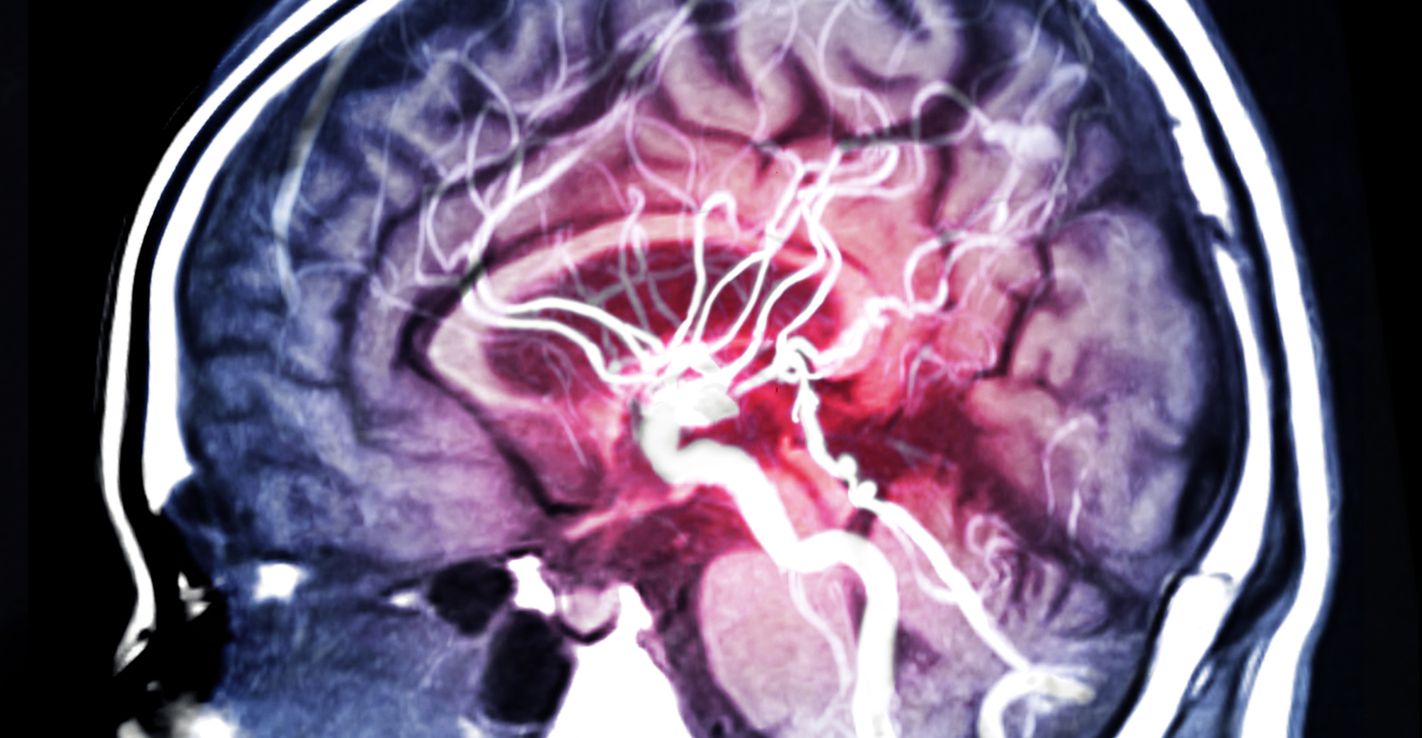

Cukier uruchamia w mózgu ośrodki odpowiedzialne za odczuwanie przyjemności (iStock)

Okazało się, że już po 12 dniach lekarze zaobserwowali zmiany w mózgu. Szczególnie w obszarach odpowiedzialnych za przetwarzanie dopaminy i opioidów. Ten drugi układ został aktywowany już po pierwszej dawce cukru. Jest on związany z tym, czy odczuwamy przyjemność, a także z naszym ogólnym samopoczuciem.